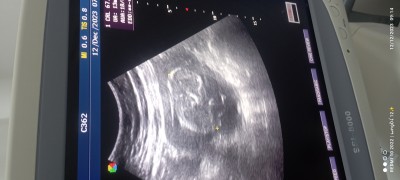

Merhaba kızlar 13+5 haftalık hamileyim az önce kontrolüm vardı doktor baktı ama cinsiyetini göstermedi şöyle bi bakarak tahminde bulunurmusunuz şimdiden teşekkürler

image